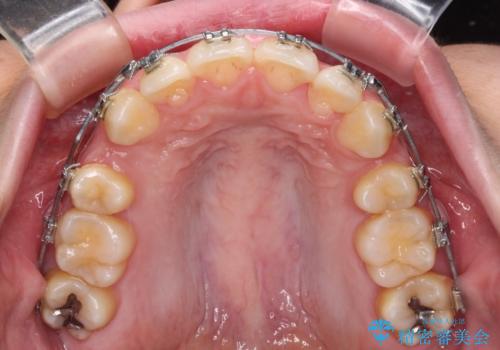

- 矯正装置

- メタルブラケット

下顎骨の左右差や、上顎骨の前方位などが認められたため、上下左右の第1小臼歯4本を抜歯し、ワイヤー装置にて矯正治療を行うこととしました。

骨格的な左右差がありましたが、何とか当初予定していた期間で、左右対称の咬み合わせに仕上げることができました。